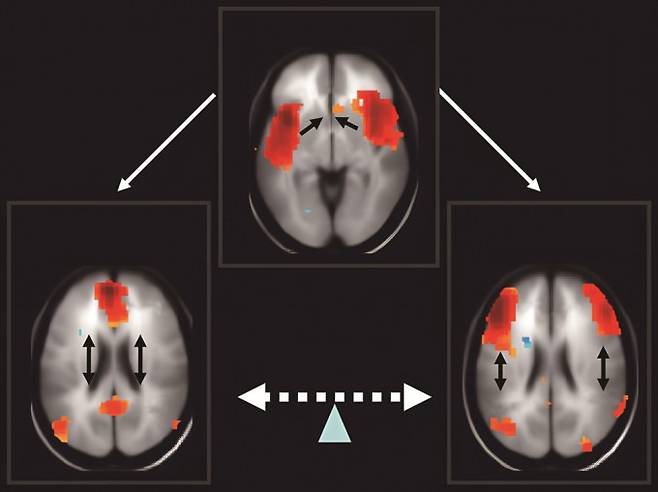

그러나 참가자 모두가 자각몽을 꿀 수 있는 것은 아니었습니다. 우충완 기초과학연구원(IBS) 뇌과학이미징연구단 부연구단장은 "잠 잘 때는 이성, 논리에 해당하는 뇌 부분이 거의 작동하지 않는다"며 "그때 해당 부분이 활성화된 사람만 자각몽을 꿀 수 있다"고 설명했습니다.

그다음 뇌는 깨어 있을 때 활성화되는 영역이자 논리와 이성을 가지고 과제 수행하는 영역인 전두두정엽 신경망의 활동을 줄어들게 만들어요. 그래서 꿈이 앞뒤가 맞지 않아도 이상하게 느끼지 않거나 평소에 억누르고 있던 생각, 불안 등이 꿈으로 나타나게 되는 것입니다.

잘때는 그 신경망이 거의 작동하지 않아서 꿈으로 나오는 것입니다. 예를 들어 외상 후 스트레스를 겪으면 트라우마 경험이 기억으로 저장되고 트라우마 기억이 뇌에서 자주 활성화돼 꿈에서도 계속 나오는 거예요."